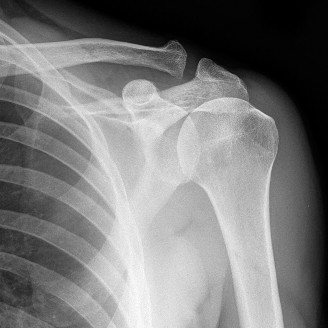

A 21-year-old, right-hand-dominant, male, college swimmer presents to clinic complaining of gradually worseni…